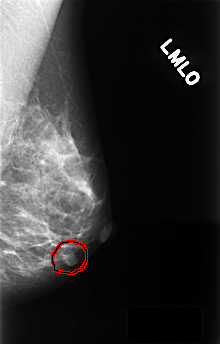

C_0386_1.LEFT_MLO

FILE: C_0386_1.LEFT_MLO.OVERLAY

TOTAL_ABNORMALITIES 1

ABNORMALITY 1

LESION_TYPE MASS SHAPE LOBULATED MARGINS CIRCUMSCRIBED

ASSESSMENT 3

SUBTLETY 5

PATHOLOGY BENIGN

TOTAL_OUTLINES 1

BOUNDARY